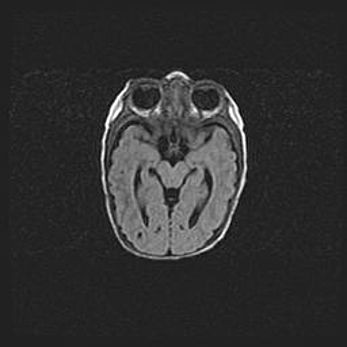

Наружная гидроцефалия с возможной атрофией височных областей.

Возраст: 28 дней

Вес: 3670 г

Пол: мужской

Окружность головы: 38 см

Срок гестации: 40 недель

Гидроцефалия головного мозга у новорожденных – это заболевание, которое характеризуется скоплением избыточного количества спинномозговой жидкости в желудочковой системе головного мозга в результате затруднения её перемещения от места выработки к месту поглощения в кровеносную систему или вследствие нарушения абсорбции. При открытой наружной форме гидроцефалии у новорожденных расширяются и переполняются субарахноидные пространства.

При нормотензивных  формах,  которые,  как  правило,  являются  следствием  перенесенных ишемических  повреждений  паренхимы  мозга,  возможно  сочетание микроцефалии  с нормотензивной гидроцефалией. В основе данных изменений лежит атрофия больших полушарий с преимущественной  локализацией  в  лобно-височных  областях.